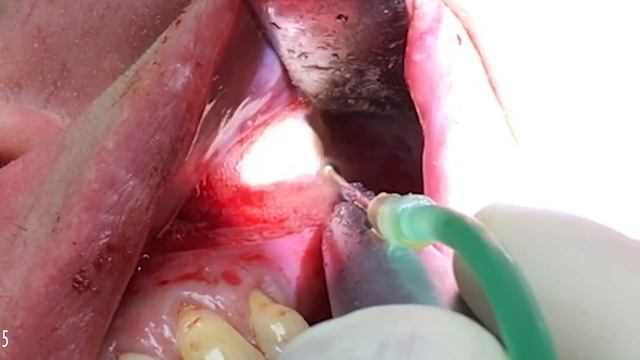

Radio frequency heats tissue from inside out which smoothes wrinkles and tightens the skin. Immediate improvements are the result of existing collagen contraction and increased blood flow. Delayed improvements result from the stimulation of new collagen formation, increased skin nutrition and the production of elastin, resulting in younger and firmer skin. The treatment works as a wonderful complement to microdermabrasion, Botox™ and injectable fillers. The 3D SculptaDerm R.F.™ is a safe, gentle and comfortable non-surgical treatment that requires no downtime. Patients can return to normal activity immediately following the procedure. Over 90% of first-time patients see immediate results, enabling you toquickly demonstrate the ability to treat issues from skin aging to cellulite. Which Parts of the Body Can Be Treated? Radio frequency is used to successfully treat the entire body. It tightens and lifts skin, from the face and neck to around the eyes. In body treatments it can treat the décolletage, abdomen, thighs, legs, buttocks and can also decrease fat pockets, cellulite, stretch marks and flaccidity. David Goldberg, M.D., of Mount Sinai’s School of Medicine N.Y., said “the mono-polar radio frequency is credited as the first non-surgical, non-invasive-skin tightening procedure that can safely and effectively treat sagging skin on the jowls, neck, arms and stomach as well as cellulite.”Купить косметическое устройство 8 в 1 TheraFace PRO https://theragunrussia.ru/theragun/?filter%5Bseriya%5D%5B%5D=5222605&order=cena:0Я очень сильно старался. Поставь лайкНаверное, самый запоминающийся и эмоциональный день со всей Недели Паркура. Несколько лет мечтал посетить Красноярские столбы и вот наконец мечта исполнилась, организаторы сильно постарались, за что им отдельный респект. Видео переделывал раза 3, потому что не знал каким хочу его видеть, полноценным влогом со всеми эмоциями, или динамичный видос под музыку с лучшими кадрами, всё-таки решил сделать обычный влоговый ролик для истории, а красивый может потом сделаю.Join IVF expert Dr. Randy Morris for a behind the scenes look at what happens before, during and after the egg retrieval at a world class IVF laboratory Chapters 0:00 Introduction 0:25 The day before the egg retrieval 0:55 Early morning preparations for egg retrieval 1:40 Patient arrival, anesthesia and final preparations 2:00 The egg retrieval begins! 2:25 Finding the eggs 3:10 Getting ready to fertilize 3:38 ICSI Dr Randy Morris MD-The BOARD CERTIFIED fertility expert with weekly TTC tips on InfertilityTV Infertility TV is your weekly source for the best medical information if you have infertility, recurrent miscarriage or are just trying to conceive. (TTC). InfertilityTV covers infertility testing, fertility treatments such as Clomid, Follistim and Crinone and fertility treatments like IUI and IVF (in vitro fertilization) One of the most popular playlists on InfertilityTV are the TTC tips which are great even you are not struggling with infertility. Dr Morris is a practicing IVF and infertility expert who sees patients at IVF1 located in the Naperville Fertility Center. Increase your "Infertelligence" ™ Subscribe to Infertility TV now!!! A new episode of Infertility TV is broadcast weekly every Thursday afternoon or visit our website at IVF1.com ******************************************* Do you want to become a patient at IVF1? ******************************************* Register online here: https://patient.ivf1.com/PatientPortal/NewPatient Or call: 630-357-6540 #EggRetrievalDay #EggRetrieval #IVFEggRetrievalHey Everyone! In this video i want to show you how to apply your eye cream or eye serum without tugging or pulling the tissue. Applying eye creams incorrectly can cause premature aging and damage to the skin tissue! Gentle application and movement is the best way to insure no damage or stretching of the thin layer tissue under the eye area. List of the products I mentioned Revital Eye Cream - https://www.guidancetoglow.com/products/bright-n-lift-eye-cream?_pos=1&_sid=318988595&_ss=r&variant=32114221482019 Follow me on my other platforms for more Skincare education Social Media Instagram | https://www.instagram.com/guidance_to_glow/?hl=en Twitter | https://twitter.com/guidancetoglow YouTube | https://www.youtube.com/channel/UCEIZNIWef-hZCBNxVRiyWwQ Website ???https://www.guidancetoglow.com/Ревизия дна гайморовой пазухи, синус-лифтинг слева, разрыв и пластика мембраны Шнейдера. Клиника Академическая стоматология, профессора Орлова А.А. Revision of the bottom of the maxillary sinus, sinus lift on the left, tearing and plastic of the Schneider membrane. Clinic Academic Dentistry, Professor Orlov A.A. ?☝️️ Запись на консультацию к профессору Орлову А.А.: ☎️ 8 (495) 699-7108, 8 (903) 508-0075 ? WhatsApp/Viber: 8 (903) 508-0075 ? Email: doctororlov@gmail.com ? Спиридоновка 9/2 www.professororlov.ru Съемка, монтаж, графика - Дмитрий Золотов dmitriy@zolotow.ruFormlabs 3Shape Materials Library: https://drive.google.com/drive/folders/1KiDGU3XE8oWoRJubrfcX2Zf0FNTtlkLF?usp=sharingAvailable exclusively at The Clinic, the Ultraformer Skin Micro-Needling treatment is the latest innovation in skin rejuvenation and re-texturisation. Ultraformer uses Ultrasound to penetrate the deeper layers of the skin, causing heat to stimulate the collagen, resulting in the tightening and firming of the skin. We then follow with the SkinPen to re-texturise the top layers of the skin, helping to reduce fine lines, visible pores, pigmentation and scarring. BEST FOR 1. Non-invasive skin lifting, tightening and resurfacing. 2. Targeting two different depths of skin including the structure and the surface for most effective results. 3. Major event preparation - impressive results with minimal downtime. Learn more about the Ultraformer Skin Needling via the link below. https://www.theclinic.net.au/pages/ultraformer-skin-needling For more information visit our website https://www.theclinic.net.au/ Follow us on Instagram https://www.instagram.com/theclinicau/ Follow us on Facebook https://www.facebook.com/TheClinicAU/【CHAT RULES】 Please read the following rules so everyone can enjoy the stream! 1) Be respectful of others in the chat. 2) Do not spam excessively, or spam in full caps. 3) Don't bring up unrelated topics or have personal conversations by tagging each other in chat. 4) English only, please. 5) No self-promo unless I mention the person. 6) No doxxing (sharing personal information about me or others) Thanks for reading! I hope you enjoy your stay! 【Tags】 GENERAL: #KoraLaila LIVE: #LaiLIVE ART: #DrawnUnder FAN NAME: #Koalala #vtuberclip #envtuber #vtuber #art #anime #drawing #overwatch2?Сегодня тот день, когда ты начнешь возвращать свою молодость и перестанешь бояться старости! Готова? Начинаем тренировку Итак, нас ждет гимнастика и массаж лица, которые избавят от: ☑ брылей, второго подбородка; ☑ асимметрии лица; ☑ морщин и дряблости шеи. Ольга Енко - омоложение лица и тела https://vk.com/econewface ✅ Как объединяя техники тейпирования, фейсфитнеса и самомассажа выглядеть моложе на 5-8 лет Вступай в клубFraxis DUO - Мощный СО2 лазер и фракционный RF. Комбинация CO2 лазера и фракционного RF для оптимальных результатов лечения по удалению растяжек, стрий, по воздействию на рубцы и фотоомоложениюExilis Reviews MA - Medical Spa Northborough http://www.renovomd.com/medispa/body-contouring/skin-tightening/ Exilis is perfect for love handles, abdomen, bra bulges, thighs, buttocks and other areas with stubborn fat. Not only that, this procedure is also perfect for smoothing facial wrinkles and folds with immediate results! This video will show you Exilis reviews MA and Exilis before and after pictures. Call (508) 393-6398 and schedule for an appointment today! RenovoMD 96 West Main Street, Northborough, MA 01532 Phone: (508) 393-6398 http://www.renovomd.com/ Exilis Reviews MA - Medical Spa Northborough